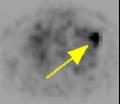

Patient below has a history of prostate cancer and melanoma with known metastasis to T7.   PET scan was performed to rule out radiation changes versus recurrence at T7.   The PET scan was negative in T7 (thus compatible with radiation changes) but serendipitously revealed marked uptake in the left upper hemithorax (Fig. 1-2 coronal and axial PET tomograms).   A subsequent CT with coronal reformation demonstrated a destructive rib lesion consistent with metastasis (Fig. 3-4).   This changed patient management who subsequently underwent chemotherapy.

Figure 1Figure 2Figure 3Figure 4